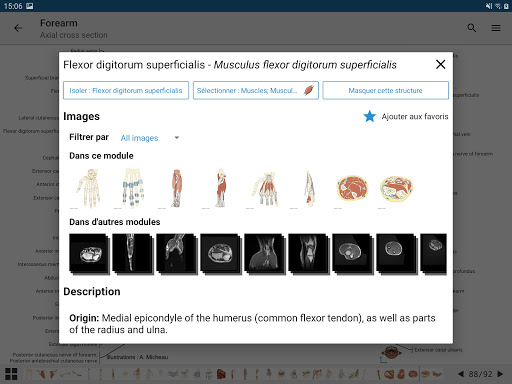

e-Anatomy tiene más de 26 000 imágenes que contienen series de imágenes en vistas axiales, coronales y sagitales, así como radiografías, angiografías, imágenes de disección, gráficos anatómicos e ilustraciones. Todas las imágenes médicas fueron etiquetadas cuidadosamente, más de 967 000 etiquetas disponibles en 12 idiomas, incluida la Terminologia Anatomica latina.

*Vista detallada mejorada de partes anatómicas para una identificación más fácil en imágenes del módulo actual y otros.

- "Filtrar por", en la vista de detalles ahora puede filtrar las imágenes que contienen la estructura anatómica por modalidad